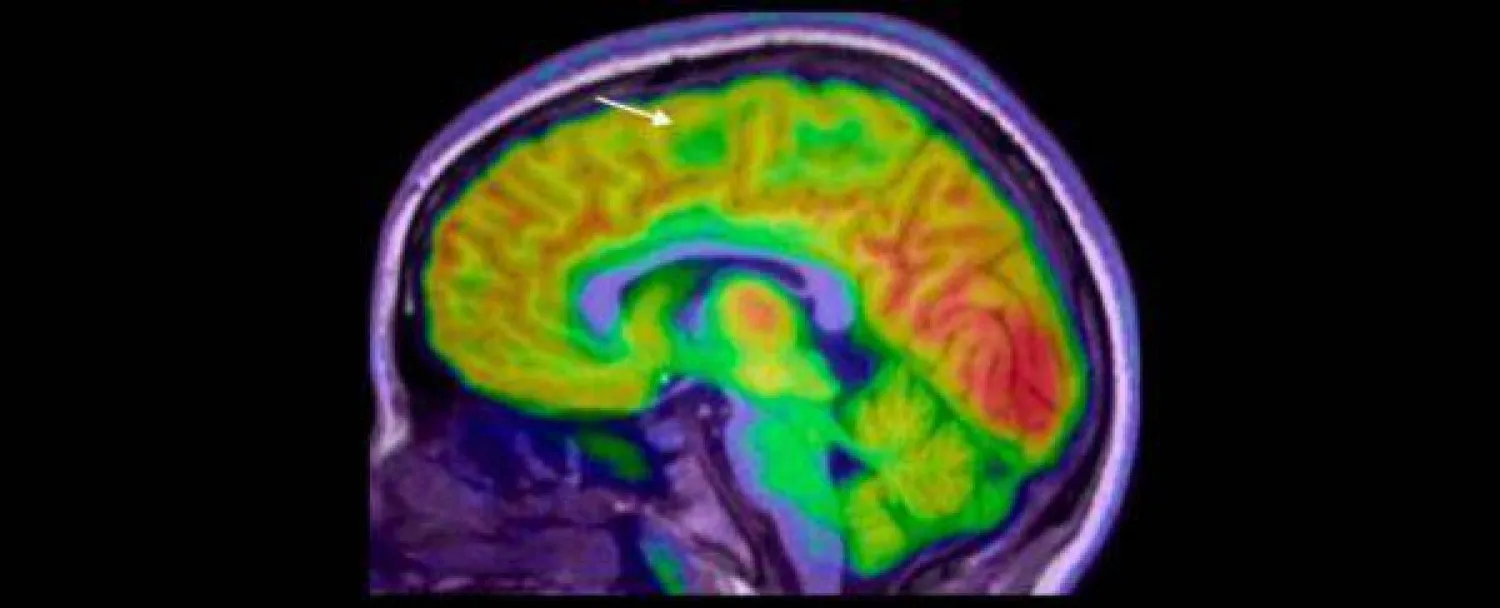

نجح فريق بحثي من «معهد مردوخ لبحوث الأطفال» (Murdoch Children's Research)، والمستشفى الملكي للأطفال، بملبورن في أستراليا، في تطوير جهاز لتشخيص الصرع بالذكاء، يستطيع رصد وجود خلل في أنسجة القشرة المخية، لا يمكن رصده من خلال فحص الأشعة العادي.

وأوضحت الدراسة التي نُشرت في نهاية شهر سبتمبر (أيلول) من العام الحالي، في مجلة «الصرع» (Epilepsia)، أن الجهاز الجديد قادر على التشخيص بدقة لأي خلل صغير في أنسجة القشرة المخية، ما يؤدي إلى تدخلات جراحية أسرع لعلاج حالات الصرع العنيفة، ومن ثَمَّ تقليل تكرار النوبات، وتحسين نتائج النمو على المدى الطويل.

قام الباحثون باستخدام التصوير بالرنين المغناطيسي لتدريب الجهاز الجديد، وبعد ذلك قاموا بتقسيم الأطفال إلى مجموعتين للتدريب، كما استُخدمت مجموعة منفصلة من فحوصات البالغين للتحقق الإضافي من أداء الجهاز.

ومن خلال فحص أشعة الرنين المغناطيسي، تمكن الجهاز الجديد من تشخيص معظم الحالات بنسبة نجاح بلغت 94 في المائة. ومن بين 17 طفلاً في المجموعة التجريبية، خضع 12 منهم لعملية جراحية، وتعافى 11 منهم الآن من النوبات.

أكد الباحثون أن اكتشاف وجود الخلل في نسيج القشرة المخية من خلال فحوصات الرنين المغناطيسي الروتينية، يُعد أمراً بالغ الصعوبة؛ حيث يتم التعرف على أقل من نصفها فقط في أول فحص للطفل، ما يؤخر التشخيص، ومن ثَمَّ يحرم الطفل من فرصة إجراء الجراحة في وقت مبكر، وكلما طالت مدة معاناة الطفل من النوبات شديدة الحدة، زاد احتمال إصابته بصعوبات التعلم، بما في ذلك الإعاقة الذهنية.